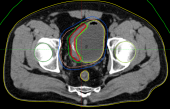

病例展示二:前列腺癌

XXX,男,64岁,主诉:间断性会阴部疼痛10月,确诊为前列腺癌7月。盆腔核磁:前列腺偏左侧异常强化占位,多考虑前列腺Ca,并左侧精囊腺受侵可能,盆腔左侧略大淋巴结。前列腺癌标志物提示:TPSA 88.67 ng/ml,FPSA 3.84 ng/ml。病检:(前列腺穿刺组织左侧)前列腺腺泡腺癌,Gleason评分4+3=7分;(前列腺穿刺组织右侧)Gleason评分3+3=6分。诊断:1、前列腺恶性肿瘤 双侧 腺泡腺癌Gleason评分4+3 =7分 cT3bN0M0 III期 KPS评分:80分。治疗方案:醋酸戈舍瑞林缓释植入剂 10.8mg 皮下注射、比卡鲁胺胶囊 50mg 口服 1次/天”全身治疗,并行前列腺癌碳离子治疗,剂量:57.6 Gy(RBE)/16 Fx。